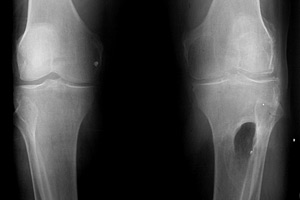

This rarely-seen case illustrates the strength of the knee joint after sustaining a major deformity; patient was able to retain mobility for many years despite extent of damage (as shown in central tibia, second-longest bone in the human body structure surpassed only by the femur).

His X-Ray showed severe osteoarthritis with deformity and fragments of metal and bullets left behind.